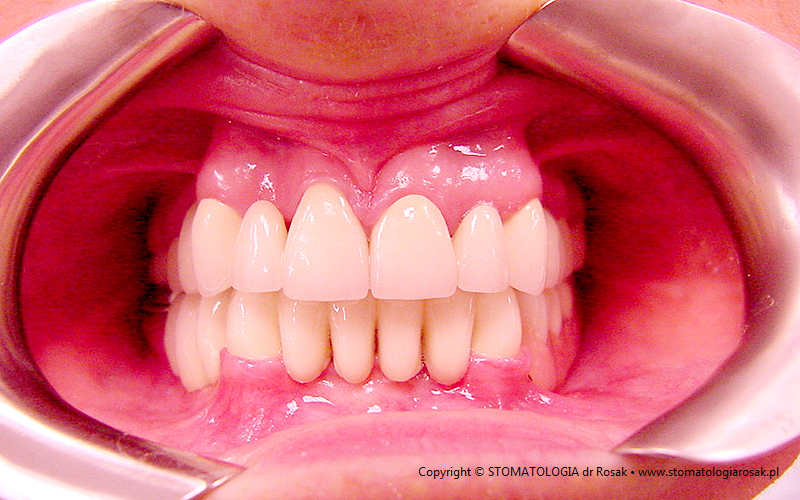

2. Pacjent z licznymi wypełnieniami (plombami), zgryzem głebokim, zaburzona estetyka

i funkcja układu narządu żucia (diastema).

| 2a. Pacjentka przed leczeniem |

2b. Gotowe mosty pełnoceramiczne

na podbudowie cyrkonowej |

2c. Gotowe mosty i korony pełnoceramiczne

2d. Gotowa praca stała - korony pełnoceramiczne